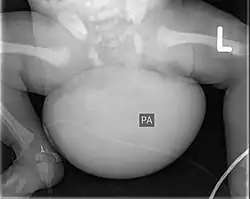

Röntgenaufnahme eines Neugeborenen mit Steißteratom

Zur Bildgebung kann der Tumor, dessen Struktur, Ausdehnung und Durchblutung gut im Ultraschall sowie in der Kernspintomographie dargestellt werden, im Röntgenbild können Kalk- und Knochenanteile sichtbar werden.[4]